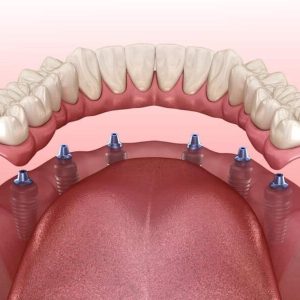

6 implanton nyugvó fogsor

A rögzített fogpótlás implantátumon nemcsak azoknak szól, akik teljesen fogatlanok, hanem azoknak is, akik még rendelkeznek fogaikkal, de azok menthetetlenek, és egy stabil, megbízható megoldást keresnek a jövőre nézve.

- Stabil és kényelmes – Nem mozdul el evés vagy beszéd közben, teljes biztonságérzetet ad.

- Természetes érzés – Mintha a saját fogai lennének, nem kell kompromisszumot kötnie.

- Gondtalan étkezés – Bármit ehet, nincs többé korlátozás a kedvenc ételei között.

- Hosszú távú megoldás – Az implantátumok évekig biztosítják a komfortot és a funkcionalitást.

- Egészségesebb íny és állkapocs – Megakadályozza a csontvesztést, amely foghiány esetén elkerülhetetlen lenne.